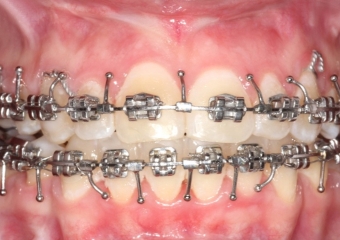

Mordida inicial